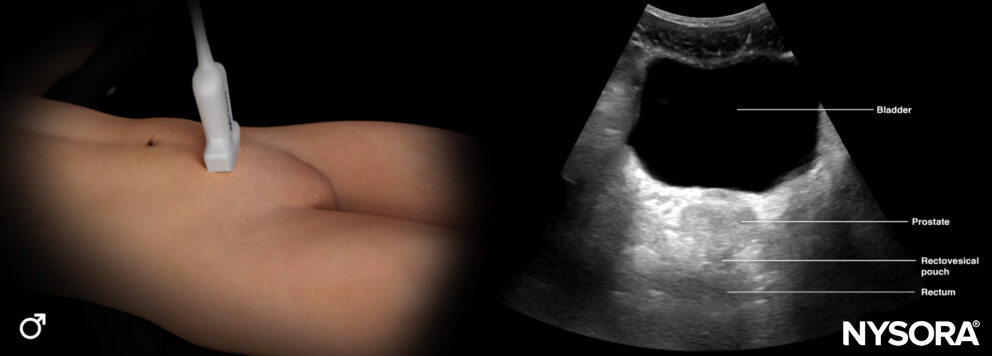

This view assesses the presence of free fluid in the pelvis.

- Position the transducer just above the pubic bone in the midline between the umbilicus and the pubic bone.

- The bladder can be used as an internal anatomical landmark to scan the area behind and lateral to the bladder for free fluid (rectovesical pouch in men and the rectouterine pouch or pouch of Douglas in women).

Sonoanatomy of interest in males:

Transducer position and ultrasound anatomy of the male pelvis.

Transducer position and reverse ultrasound anatomy of the male pelvis.